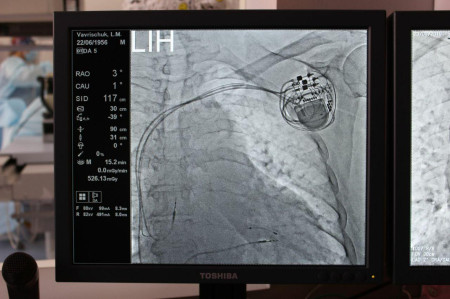

Так, учора, 20 вересня, у Ковельському МТМО успішно провели постановку трикамерного кардіостимулятора. Цю складну операцію провели без жодного розрізу, через невеличкий прокол.

З її слів, трикамерний кардіостимулятор встановили пацієнтці з повною блокадою лівої ніжки пучка Гіса, серцевою недостатністю важкого ступеня та фракцією викиду всього 12%.

«Імплантація даного приладу дозволила синхронізувати роботу всіх відділів серця. Вона збільшить скоротливу здатність серцевого м’яза та значно покращить рівень життя пацієнтки. Щиро дякуємо Парацію Олексію Зіновійовичу, Якушеву Андрію Володимировичу, Леончуку Володимиру Леонідовичу, Грабар Лідії, Агнессі Паризян, Голубу Олександру Миколайовичу, Гусці Андрію Богдановичу, директору Національного інституту серцево-судинної хірургії імeні М.М.Амосова, академіку НАМН України Василю Лазоришинцю, Ковельському міському голові Олегу Кіндеру та депутатам міської ради, начальнику Управління охорони здоров’я Волинської облдержадміністрації Ігорю Ващенюку за сприяння розвитку кардіохірургії в Ковелі», - повідомила медик.